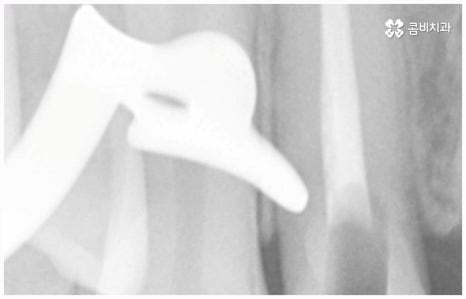

임플란트는 관리를 철저하게 해 준다면 거의 반영구적으로 쓸 수 있다고 알려져 있을 만큼 잘 유지 관리하는 것이 굉장히 중요한데, 그 첫 단계가 정확한 위치와 각도로 식립하는 과정이라고 할 수 있어요. 임플란트가 잘못된 위치에 식립되거나 너무 깊게 또는 얕게 식립되면 교합이 잘 맞지 않고 저작 활동을 할 때 무리가 가 잇몸병을 유발함으로써 임플란트의 수명을 줄일 수 있기 때문인데, 이때 임플란트 제작시 커스텀 지대주를 사용하면 환자분들의 구강 구조에 정확하게 맞는 각도로 보철물을 식립할 수 있어서 더욱 편안한 사용을 할 수 있을 거예요. 식립 후 너무 많이 딱딱하거나 끈끈한 음식은 조심하시는 편이 좋으며, 이후 꾸준하고 지속적인 검진 및 스케일링 치료를 통해 위생을 청결하게 해 주면 임플란트 수명을 연장하는데 도움이 될 수 있습니다.